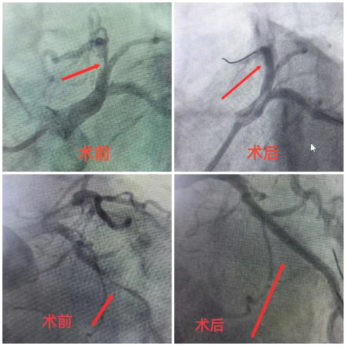

患者田先生,因“反复心累、胸闷4+年加重7天”入院,入院后考虑冠心病可能性大,有明确手术指征,随后行冠状动脉造影检查,确诊为冠心病。确诊后,内科一病区医生团队为患者实施了冠状动脉支架植入术。术后,田先生心累、胸闷症状明显减轻,恢复良好,生活质量显著提升。

冠心病,是冠状动脉因粥样硬化导致血管狭窄或堵塞,引起心肌缺血、缺氧的心脏病。冠状动脉支架植入术是一种微创介入治疗,医生通过患者桡动脉或股动脉,将一根细细的导管沿着血管送至冠状动脉狭窄或堵塞的部位,手术创伤小、恢复快,能有效恢复心肌供血。